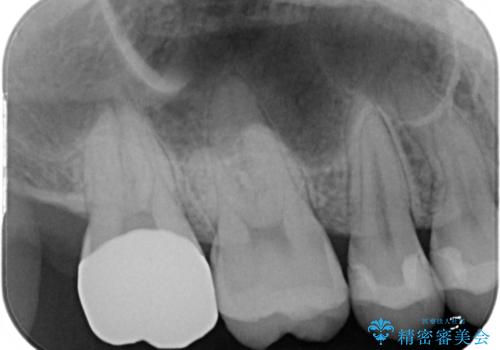

広範囲にわたる虫歯をセラミックで治療

- 他県より引っ越しをされたため、途中になってしまっている虫歯治療の続きをしてほしいと来院された患者様です。

痛み等の自覚症状はありませんでしたが、広範囲にわたる虫歯を認めたため、セラミッククラウンによる治療を行いました。

今回のケースでは、一番奥の歯の後ろ側に向かって虫歯が進行していました。一番奥の歯は元々の歯の高さが低いことが多く、被せ物が割れるリスクが増加したり、被せ物が外れやすくなる場合があります。歯牙切削量の少ないゴールドアンレーもご提案しましたが、セラミックをご希望されたため、今回はクラウンによる治療を行いました。